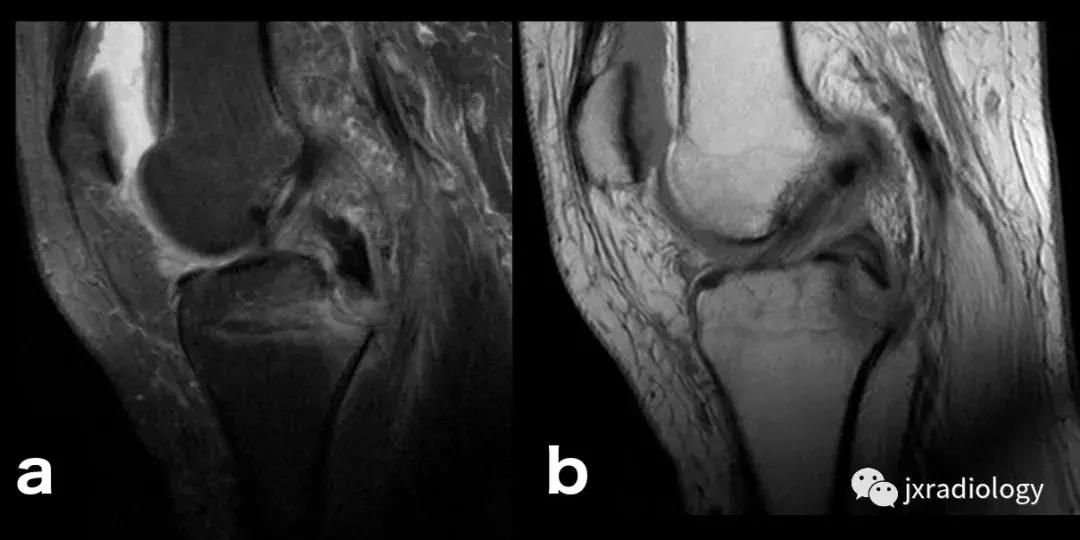

图8:创伤性骨髓水肿,髌骨脱位的典型病例:青年人,髌骨一过性脱位和挫伤的横断面(a,b,c),冠状面(d,e)和矢状面(f)的PD-FS-WI图像 :股骨外侧髁的前外侧和髌骨下内侧的故事水肿。对于进行运动的青少年或年轻人来说,在弯曲时需要膝盖扭转运动的情况更为常见。如该患者患有髌骨骨软骨损伤(*)和内侧髌股韧带(MPFL)撕裂(箭头)。

图9:外伤性骨髓水肿,典型的轴移损伤模式:在矢状面上的PD-FS-WI。这类非接触性损伤常见于滑雪者或美式足球运动员。这种模式是由于外翻负荷作用于屈曲或半屈曲膝关节,与胫骨外旋或股骨内旋相结合。水肿范围包括胫骨外侧平台的后方和股骨髁间(a)附近的股骨外侧髁的中部[3]。膝关节的屈曲程度决定了股骨外侧髁损伤的确切位置。有时,如a所示,发生股骨外侧髁冲击性骨折。另一个经常出现的骨挫伤部位是内侧胫骨平台的后部(如b所示)。ACL在这种创伤中经常被撕裂,因此当识别出这种损伤时应该对韧带进行彻底的评估。